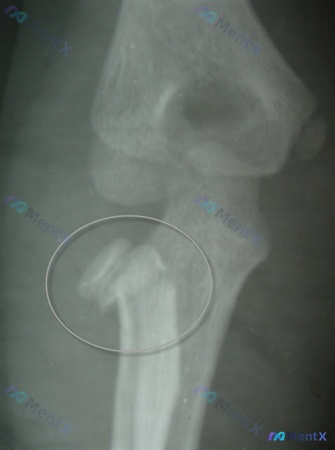

整理到一个12岁男性的肘部创伤病例: - 8英尺跌落,手掌撑地受伤 - 急诊X光显示桡骨颈移位 - 镇静下行闭合复位,复查X光(正位)显示:桡骨头/颈仍有明显骨质连续性中断,碎裂/多块骨碎片,移位分离,台阶感明显,肱桡关节解剖异常,局部软组织肿胀 目前的问题是:下一步最合适的治疗是什么?